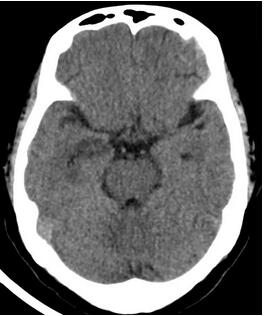

手术过了五天,神经内一科为王阿姨复查CT影像。可以看出,相比较手术前,右侧大脑中动脉的高密度影已经明显减轻了。

目前王阿姨的状态已经好了很多,相信再过几天,王阿姨就可以回家,和家人一起过一个幸福快乐的新年。